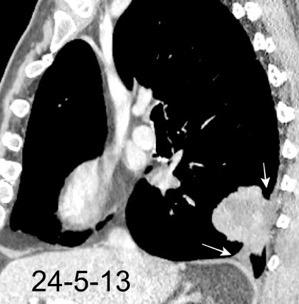

Marzo 2014: Perforación longitudinal distal secundaria a episodio de vómito (síndrome de Boerhaave). Derrame pleural izdo. que evoluciona a empiema.

Wang C-T et al. Tension hydropneumothorax in a Boerhaave syndrome patient: A case report . World J Emerg Med, 2021. Katabathina V et al. Nonvascular, nontraumatic mediastinal emergencies in adults:a comprehensive review of imaging findings. Radiographics. 2011.